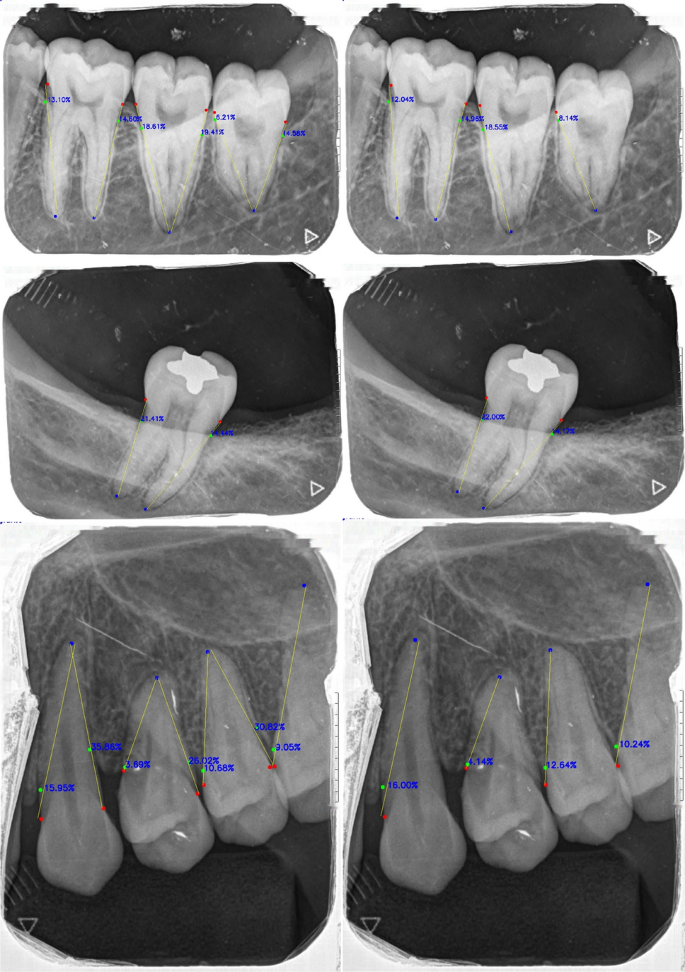

The predicted keypoints were used to calculate bone loss severity using the proposed mathematical method. The estimated severity values were compared with ground truth annotations using the Intra-class correlation coefficient (ICC). The ICC values were 0.851, 0.824, and 0.801 for training, validation, and test sets, respectively, indicating consistent agreement. Figure 9 illustrates severity estimations derived from both predicted and ground truth points, including best-fit lines and calculated severity values.

Comparison of ground truth (left) and predicted (right) alveolar bone loss severity. Red points represent the cementoenamel junction (CEJ), green points indicate the intersection between the alveolar crest bone level and the tooth surface, and blue points mark the apex of the tooth. Yellow lines represent the min-max line53. Bone loss severity are displayed on the corresponding sides of each tooth. Ground truth severity were calculated using manually annotated points, while predicted severity were derived from the model’s predicted points.

Alveolar bone loss severity

According to Koo and Li (2016)58, ICC values between 0.75 and 0.90 indicate good reliability. Based on the ICC value from the test set, the proposed severity estimation method produces results consistent with expert evaluations, demonstrating its potential as a decision-support tool for periodontal assessment.